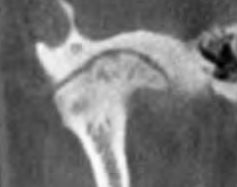

cone beam CT

The patient is seated in the chair. The machine rotates around the head & emits a collimated cone-shaped x-ray beam. The scan takes 9.6 seconds. 512 computer files are generated. With special software, it is possible to create any number of views from any angle in both 2D and 3D. The examples below show some of the possibilities of this technology.

tmj